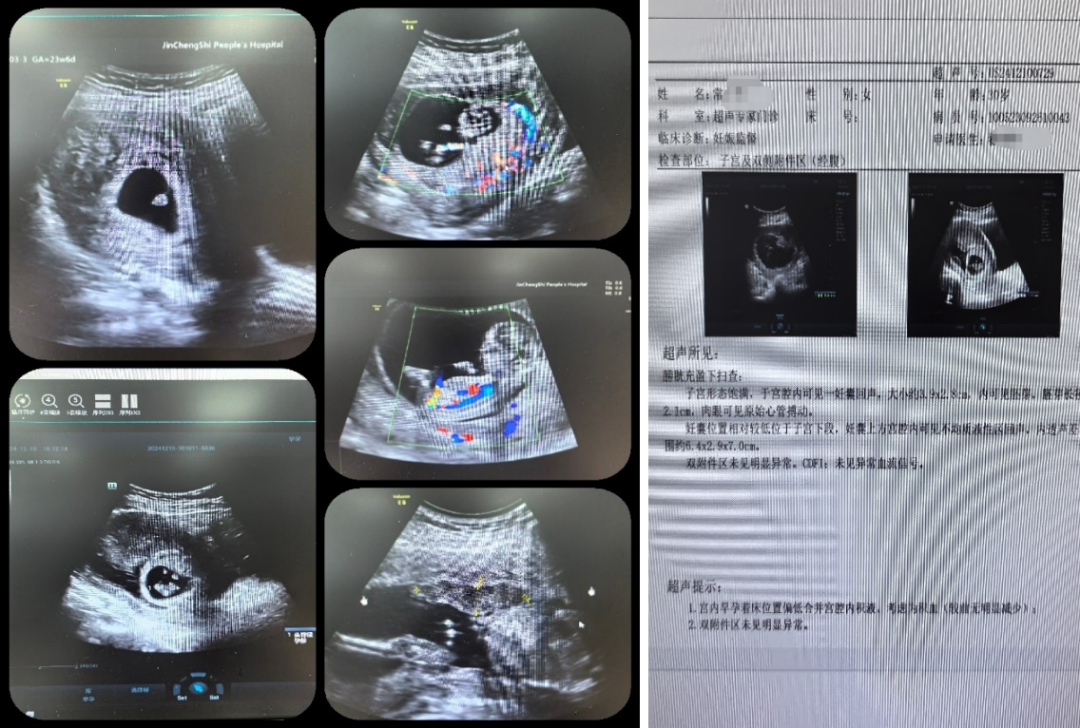

30 岁的常女士曾有过一次流产经历,今年再次怀孕的她满心期待,却在孕早期遭遇了危机 —— 出现阴道大量出血症状。经彩超检查发现,她存在绒毛膜下巨大血肿,妊囊已降至子宫下段,随时可能再次流产。这一消息让常女士和家人心急如焚,他们辗转多家医院就诊,得到的答复均是此次妊娠保胎希望渺茫。在绝望之际,常女士抱着最后一丝希望来到晋城市人民医院,接诊的正是产科擅长复发性流产保胎治疗的田韵凌副主任。

田韵凌副主任对常女士的病情进行了全面细致的评估,结合她的病史和检查结果,量身制定了个性化的保胎方案。方案涵盖药物治疗、营养支持、心理安抚等多项综合措施,全力为常女士腹中的小生命保驾护航。治疗期间,医护人员时刻密切关注常女士的身体状况,根据病情变化及时调整治疗方案。同时,他们耐心指导常女士如何正确卧床休息、合理安排饮食,确保每一个护理环节都能为胎儿的健康成长创造有利条件。